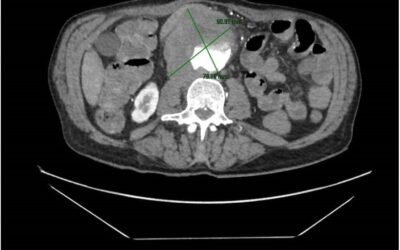

Aortoenteric fistula: Endovascular aortic aneurysm repair

Drs. Teresa González (cardiovascular surgeon) and José Joaquín Muñoz (Interventional Vascular Radiologist) publish a...